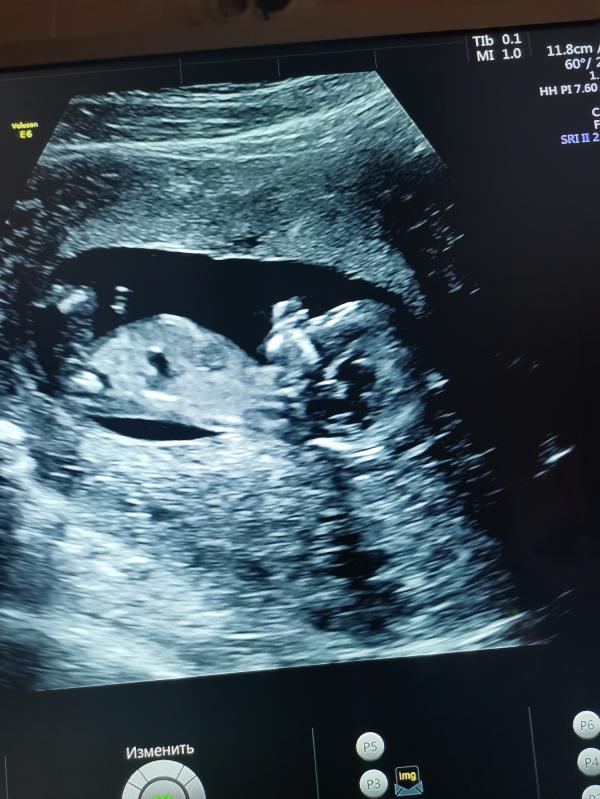

Оставлю это здесь на память 😀Наш первый скрининг, срок 12+6. Очень переживала по поводу этого дня. На УЗИ сказали всё хорошо, скорее всего девочка. Во время УЗИ подпрыгивает в животике, так радостно было на душе, мне кажется у меня улыбка до ушей была🤗